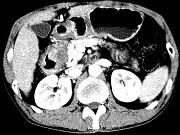

问题 女,63岁,右上腹疼痛,呈不规律性钝痛,伴恶心,时有呕吐,呕吐物为胃内容物混有胆汁,CT检查如图,最可能的诊断是()

选项 A.十二指肠克罗恩病 B.十二指肠结核 C.十二指肠癌 D.十二指肠淋巴瘤 E.十二指肠平滑肌瘤

答案 C